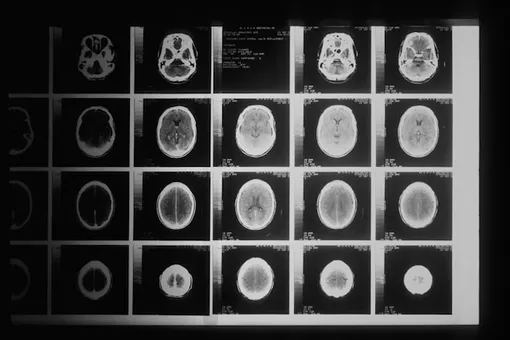

Затем исследователи оценили, сколько клеток в зубчатой извилине, области гиппокампа, которая, как известно, генерирует нейроны на протяжении всей жизни. В группе, получавшей SedV, было примерно на 50% больше нейронов, чем в контрольной группе. Фактически, мыши, получавшие SedV, были практически идентичны мышам, получавшим плацебо, что указывает на то, что стимуляция мозга была характерна для вызванных физическими нагрузками ВВ.

И, что немаловажно, несмотря на то, что в результате переливания крови появилось больше новых нейронов, в общей структуре гиппокампа не произошло каких-либо существенных изменений. Это подтверждает результаты предыдущих исследований, которые показали, что рост нейронов, вызванный физическими упражнениями, уравновешивается естественными процессами.